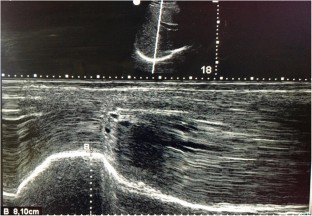

Fig. 1

Fig. 2

Fig. 3

Fig. 4

Fig. 5

Fig. 6

Fig. 7